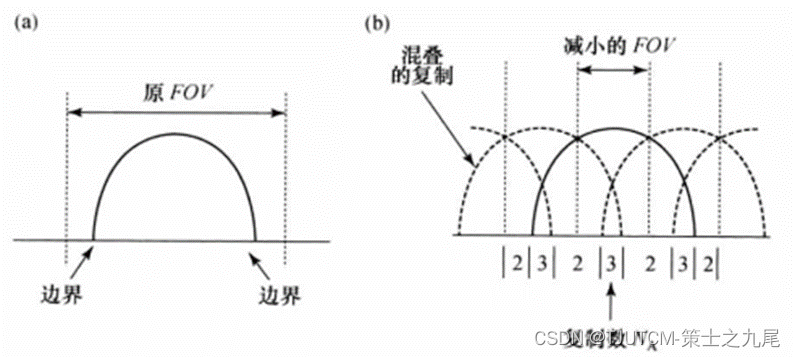

(a)图为正常的FOV。

(b)图为对于并行成像R=3降低的FOV。在y方向各位置混叠的复制数NA依赖于边缘位置和加速因子R。

SENSE方法要求估计线圈灵敏度,灵敏度可用另外的校准扫描来估计,校准扫描要覆盖用并行成像扫描的整个体积。另一个做法是通过用全奈奎斯特采样测量K空间中央部分,得到低分辨率灵敏度估计;而用欠采样测量K空间外围区域,以加速采集,可把这些步骤建立、集成在并行成像序列中。